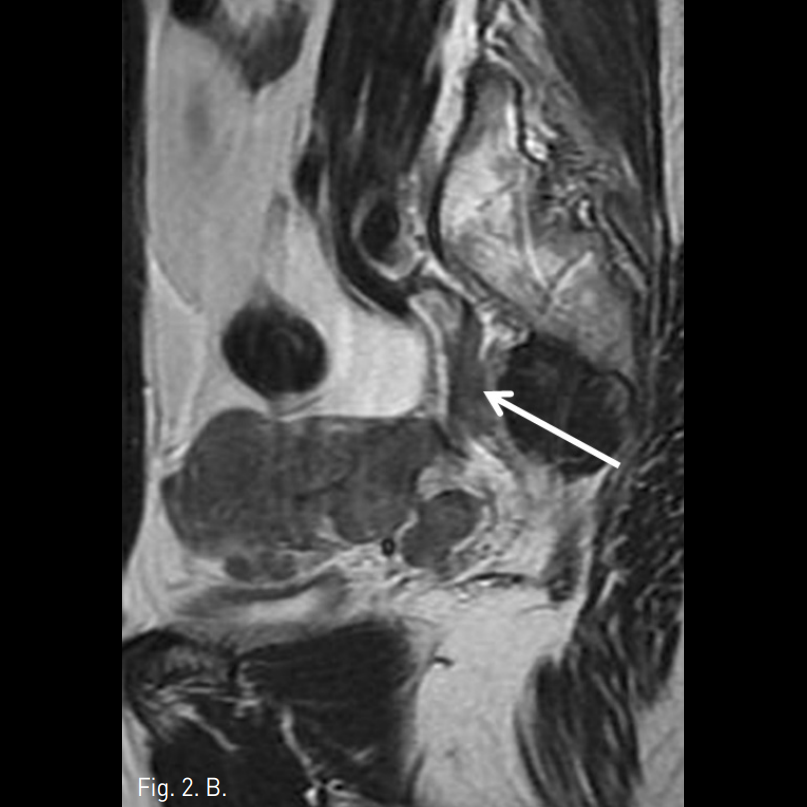

Fig. 2

A, B, C. T2 weighted sagittal MR images and Gadolinium enhanced T1 weighted image demonstrate the mass is growing along the internal iliac vein superiorly (arrows in A, B and C).